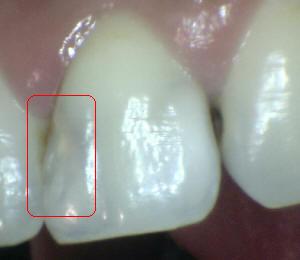

Código 4

(Caries Moderada): Sombra oscura

de dentina

subyacente al esmalte intacto con o sin interrupción localizada del

esmalte

- Esta lesión aparece como una sombra de

decoloración visible a través de una cresta marginal,

aparentemente intacta, o con pequeña micro-cavidad o perdida

de continuidad del esmalte, después del secado con aire por

5 segundos.. Las paredes vestibular o lingual

del esmalte dejan traslucir dentina decolorada.

Este aspecto se ve a menudo con más facilidad cuando el

diente está húmedo. El área oscura es una sombra intrínseca

que puede aparecer como gris, negro-azul o marrón-anaranjado

- Puede utilizarse

una sonda periodontal para identificar

la micro-cavidad en esmalte o discontinuidad < 0,5 mm.